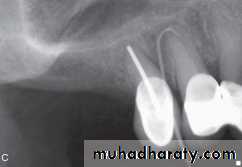

COLLEGE OF DENTISTRYSwelling in the anterior part of the palate is most frequently associated with an infection present at the apex of the maxillary lateral incisor or the palatal root of the maxillary first premolar

A swelling in the posterior palate is most likely associated with the palatal root of one of the maxillary molars